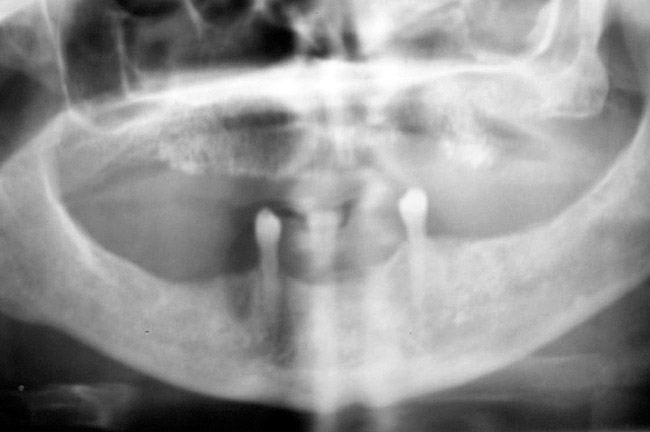

Figure 18  Panoramic radiograph showing decreased bone density.

Figure 18

As stated earlier, spontaneous osteonecrosis is also possible. Figure 14 shows a case of spontaneous BRONJ resulting from wearing an ill-fitting denture. The patient had noticed the foreign material, but chose not to act on it. When the material was removed in the dental office (Figure 15 and Figure 16), blood streamed from the nose so severely that the patient had to be sent to an ear, nose, and throat (ENT) physician. The ENT took a computed tomography scan, which showed a large radiolucency in the upper left quadrant where the foreign material once had been (Figure 17). A review of the radiograph (Figure 18) showed that bone in the maxillary arch had decreased mineral density compared with the mandible. The biopsy report found necrotic bone with organisms consistent with actinomyces. These findings were consistent with biopsies found in the literature.22 When the patient returned for a 1-week follow-up, she still had signs of infection and the site had a foul odor and a discharge (Figure 19). The patient was informed that she should follow up with the ENT and return to the dental office after the infection had been resolved.